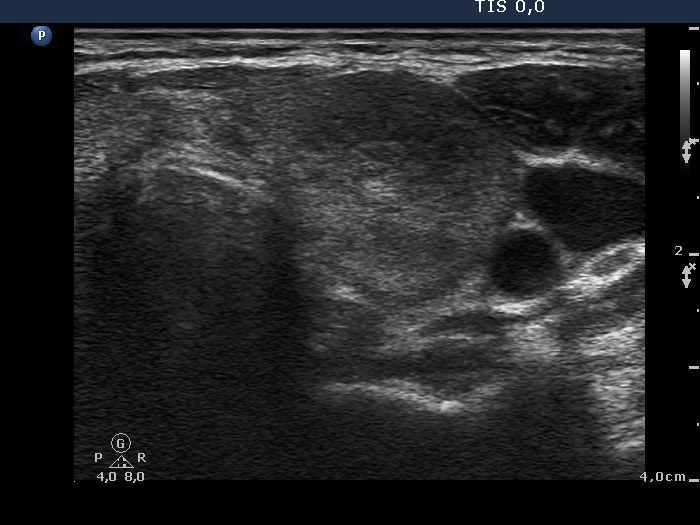

Ultrasonography: The right lobe was moderately hypoechogenic, while the left one was echonormal-minimally hypoechogenic. Several more hypoechogenic areas with ill-defined borders were found. The vascularization was decreased.